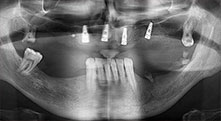

Импланти

Четирите импланти са поставени на място, както е планирано. Дисталните молари на горна челюст все още могат да се използват за фиксиране на протезата, която е сложена един месец след имплантиране.